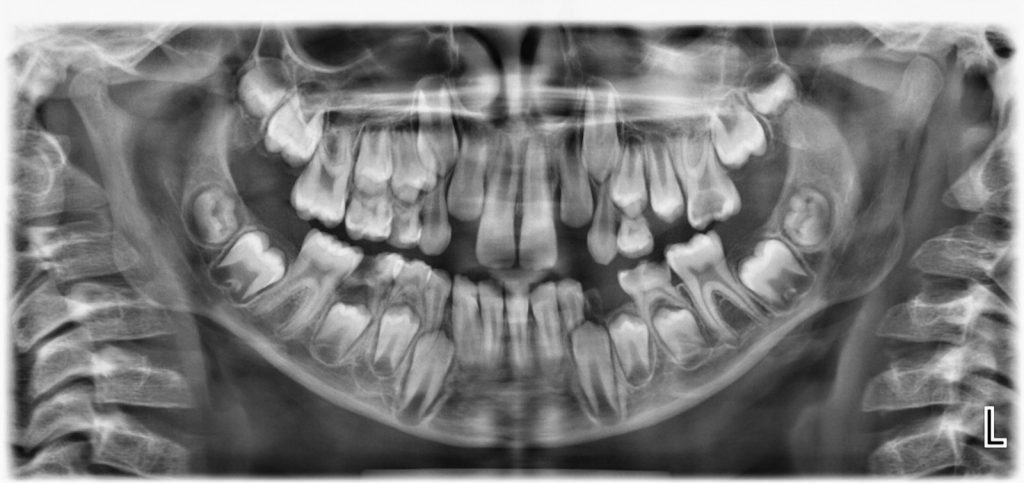

Dečiji digitalni ortopan

Detaljan prikaz obe vilice sa svim zubima, kao i sa zubima koji još uvek nisu iznikli.

Razlika u odnosu na snimanje odraslih pacijenata je u tome što se najmladji pacijenti  snimaju po posebnom programu i protokolu koji podrazumeva:

• Kompjuterski redukovanu dozu zračenja

• Manje zračno polje

• Kraće vreme ekspozicije

• Posebnu dečiju zaštitnu olovnu kecelju.

Upotrebom ovih protokola doza zračenja se dodatno smanjuje i do 40 % u odnosu na odrasle pacijente, uz dobijanje standardno kvalitetnog snimka.